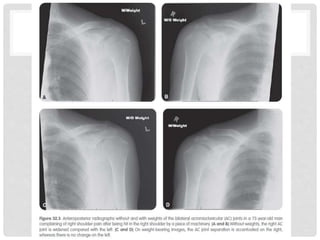

RADIOGRAPHIC EVALUATION OF THE AC JOINT

Stress Views of the Distal Clavicle & AC Joint

demonstrate instability anddifferentiate grade III AC separations from partial Grade I-II injuries. Performed by having patient hold 10# weight with injured arm. Rarely used today, since most Grade I-III AC joint injuries are treated the same anyway, and management of distal clavicle fractures depends on initial displacement and location of fracture. RADIOGRAPHIC EVALUATION OF THE AC JOINT Stress Views of the Distal Clavicle & AC Joint

RADIOGRAPHIC EVALUATION OFTHE ACROMIOCLAVICULAR JOINT • Proper exposure of the AC joint requires one-third to one-half the x-ray penetration of routine shoulder views • Initial Views: • Anteroposterior view • Zanca view (15 degree cephalic tilt) • Other views: • Axillary: demonstrates anterior-posterior displacement • Stress views: not generally relevant for treatment decisions.